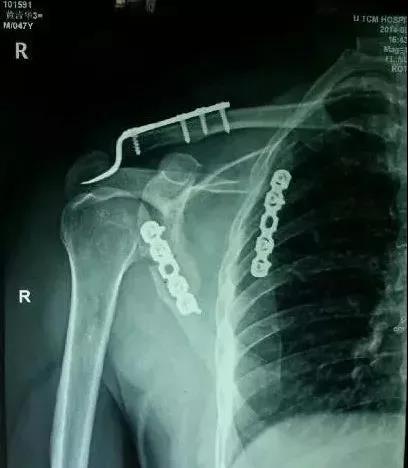

(2)肩胛带骨折

1)锁骨骨折

当骨折块伤及锁骨下动、静脉和臂丛神经时,一致认为是严重的并发症,应立即手术。

2)肩胛骨骨折

在2周之后手术,困难程度翻番。

1)肱骨近端骨折

脱位伤及腋神经、血管等,或者由于肱二头肌长头腱卡压无法复位,立即手术。